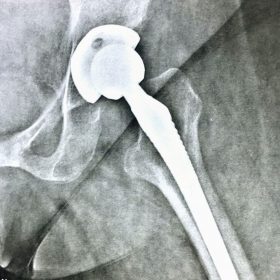

Παραδοσιακά οι αρθροπλαστικές ισχίου αποτελούνται από μια μεταλλική μπάλα – σφαίρα τοποθετημένη σε μια πλαστική κοιλότητα (κοτυλιαία πρόθεση).

Η πλαστική επιφάνεια στήριξης φθείρεται με την πάροδο του χρόνο, με ρυθμό μάλλον σχετιζόμενο με το επίπεδο δραστηριότητας του ατόμου. Αυτό έχει σαν επακόλουθο νεότεροι ασθενείς με μεγαλύτερο προσδόκιμο ζωής να έχουν αυξημένο ρίσκο αναγκαιότητας δεύτερης αρθροπλαστικής ισχίου (αναθεώρησης – Revision) επέμβαση που είναι πολυπλοκότερη και υπόκεινται σε υψηλότερο κίνδυνο επιπλοκών. Βάση των ανωτέρω, ιστορικά, η αρθροπλαστική ισχίου σπανίως εφαρμοζόταν σε ασθενείς κάτω των 60 ετών.

Χάρη στα νέα τεχνολογικά επιτεύγματα έχουν παραχθεί επιφάνειες στήριξης που ανταποκρίνονται σε μεγαλύτερα επίπεδα δραστηριότητας και αναμένεται να έχουν μεγαλύτερη διάρκεια ζωής. Αυτές οι καινούριες επιφάνειες στήριξης είναι συνήθως μέταλλο πάνω σε ειδικό σκληρότερο πλαστικό ή κεραμικό πάνω σε κεραμικό. Ως εκ τούτου, είναι τώρα πολύ πιο σύνηθες, νεότεροι ασθενείς να χειρουργούνται καθώς η πλειονότητα αυτών, που η αρθρίτιδα τους προκαλεί αφόρητους πόνους, επιλέγουν να έχουν ποιότητα ζωής από το να ζουν με τον πόνο.